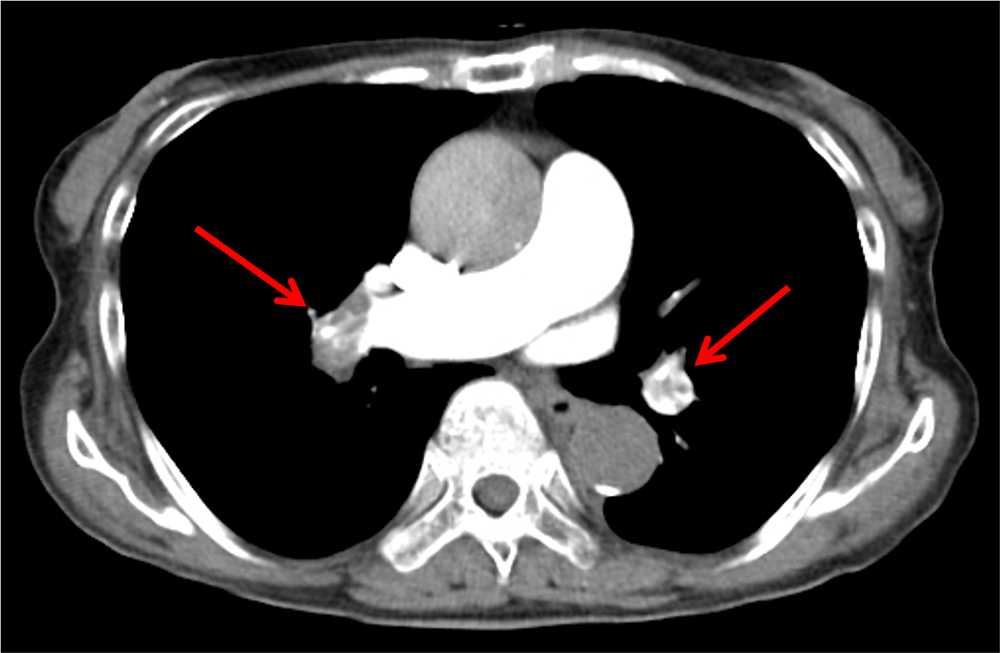

図3.図1と同時期の下腿造影CT

左膝窩静脈の造影欠損はわかりにくい。